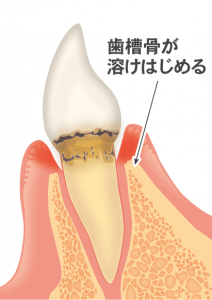

歯周病菌や噛む力の影響で、歯茎が腫れたり、歯を支えている骨(歯槽骨)が溶けてしまう病気です。

歯周病が進むとどうなるか

■歯がグラグラして抜けてしまう